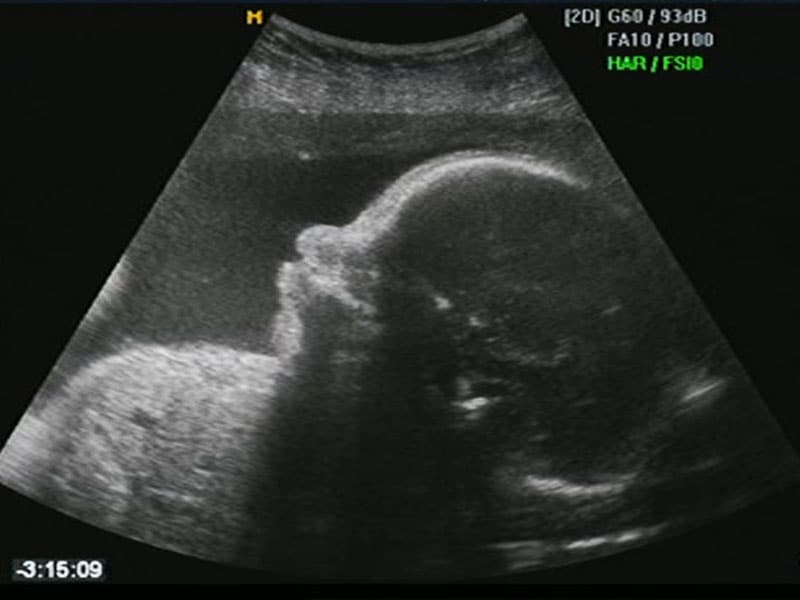

Fetoscopy is an endoscopic procedure during pregnancy to allow surgical access to the fetus, the amniotic cavity, the umbilical cord, and the fetal side of the placenta. A small (3–4 mm) incision is made in the abdomen, and an endoscope is inserted through the abdominal wall and uterus into the amniotic cavity. Fetoscopy allows for medical interventions such as a biopsy (tissue sample) or a laser occlusion of abnormal blood vessels (such as chorioangioma) or the treatment of spina bifida.

Fetoscopy is usually performed in the second or third trimester of pregnancy. The procedure can place the fetus at increased risk of adverse outcomes, including fetal loss or preterm delivery, so the risks and benefits must be carefully weighed in order to protect the health of the mother and fetus(es). The procedure is typically performed in an operating room by an obstetrician-gynecologist.